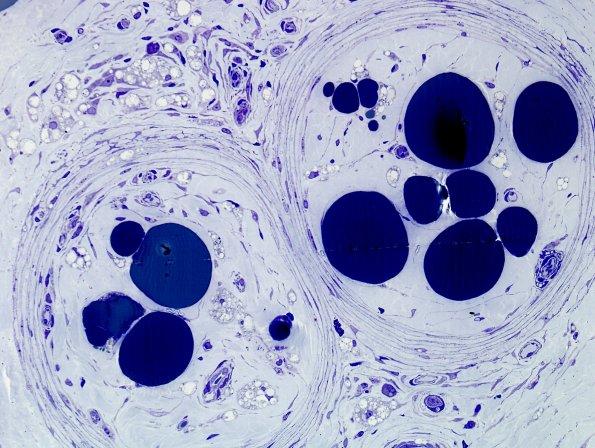

Intrafascicular lipid droplets are accompanied by endoneurial fibrosis. (plastic section)